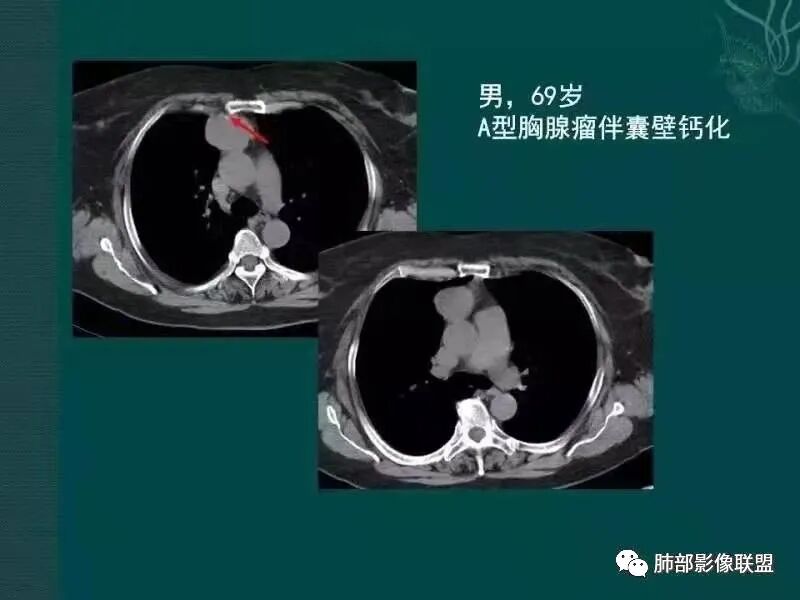

黄勇老师胸腺瘤总结

【每日晨读】胸腺瘤or胸腺癌,且听南边老师娓娓道来

胸腺瘤之罕见类型